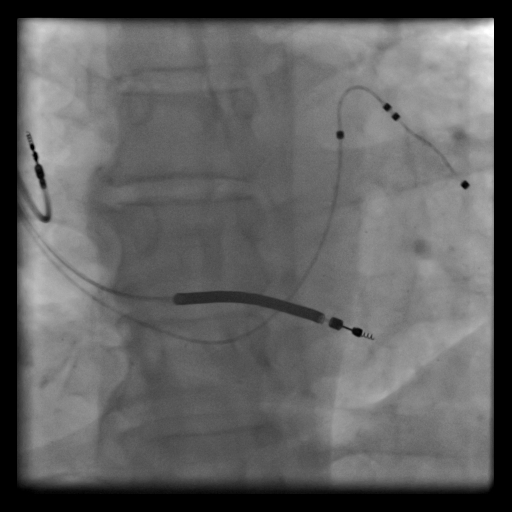

Anjiografi laboratuvarında lokal anestezi altında yapılan bir işlemdir; ICD’den farklı olarak, sol kalbi senkron uyarabilmek için koroner sinüs içine de elektrot kateter yerleştirilir.